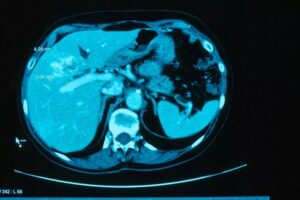

ตามรายงานยังอธิบายอีกด้วยว่า เนื่องจากผู้คนจำนวนมากชอบรับประทานปลาดิบนี้ ส่งผลให้ภาคอีสานของประเทศไทยมีจำนวนผู้ป่วยมะเร็งท่อน้ำดีสูงที่สุดในโลก ซึ่งโรคนี้ได้รับการขนานนามว่า เพชฌฆาตเงียบ ซึ่งมีอัตราการรอดชีวิตต่ำที่สุดในบรรดามะเร็งทุกชนิด หากไม่ได้รับการรักษาอย่างเร่งด่วน

ซึ่งเมื่อรับเอาพยาธิเข้าไปแล้ว จะไปฝังตัวในท่อน้ำดีเป็นเวลานานทำให้บริเวณดังกล่าวเกิดการอักเสบเรื้อรัง 30-40 ปี และพบว่า 10% จะกลายเป็นมะเร็งท่อน้ำดี หากตรวจพบเร็วก็สามารถรักษาให้หายได้ แต่ถ้าช้าก็อาจถึงขั้นเสียชีวิตได้